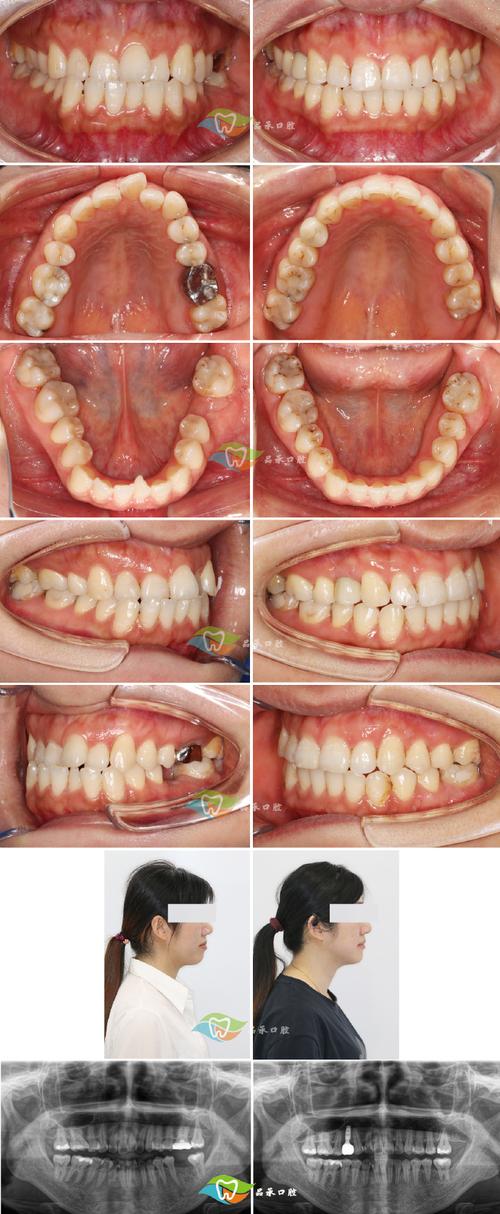

术前检查与评估

通过口腔检查、模型分析、X线片(根尖片、曲面断层片、CBCT)等明确后牙咬合异常的类型、程度及病因,判断是否存在颌骨发育问题或牙周疾病,制定个性化方案。

(图片来源网络,侵删) -